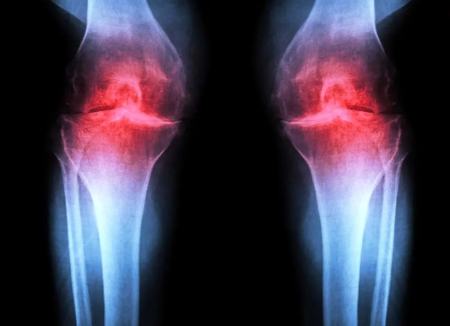

دانشمندان روشی برای بازسازی غضروف شناسایی کرده‌اند که با هدف‌گیری پروتئینی که با افزایش سن بیشتر می‌شود، آسیب مفصلی در حیوانات مسن را معکوس می‌کند و پس از آسیب، از بروز آرتروز جلوگیری می‌کند.

به گزارش فرادید، پژوهشگران دانشکده‌ی پزشکی استنفورد گزارش می‌دهند که مهار یک پروتئین وابسته به پیری می‌تواند غضروفی را که به‌شکل طبیعی در زانوی موش‌های مسن تحلیل می‌رود، بازسازی کند. در این مطالعه، درمان تزریقی نه‌تنها غضروف را دوباره ساخت، بلکه پس از آسیب‌های زانو نانند پارگی رباط صلیبی قدامی (ACL) که در ورزشکاران و بزرگسالان فعال شایع است، از بروز آرتروز هم جلوگیری کرد. نسخه‌ی خوراکی همین درمان هم‌اکنون در کارآزمایی‌های بالینی با هدف درمان ضعف عضلانی مرتبط با افزایش سن در حال آزمایش است.

این درمان به‌جای تسکین نشانه‌ها، عامل زمینه‌ای آرتروز را هدف می‌گیرد. این بیماری حادشونده مفصلی حدود یک‌پنجم بزرگسالان ایالات متحده را درگیر می‌کند و سالانه حدود ۶۵ میلیارد دلار هزینه‌ی مستقیم مراقبت‌های سلامت ایجاد می‌کند. در حال حاضر هیچ دارویی وجود ندارد که بتواند روند بیماری را متوقف یا معکوس کند و مدیریت درد و تعویض مفصل گزینه‌های اصلی درمان هستند.

آرتروز زمانی رخ می‌دهد که مفصل بر اثر پیری، آسیب یا چاقی تحت فشار قرار گیرد. کندروسیت‌ها شروع به آزادسازی مولکول‌های پیش‌التهابی و تجزیه‌ی کلاژن (پروتئین ساختاری اصلی غضروف) می‌کنند. با از دست رفتن کلاژن، غضروف نازک و نرم می‌شود و التهاب همراه، تورم و درد مفصل را (که از ویژگی‌های بارز بیماری است) ایجاد می‌کند. در شرایط عادی، غضروف مفصلی به‌ندرت بازسازی می‌شود. اگرچه برخی جمعیت‌های فرضی از سلول‌های بنیادی یا پیش‌سازِ قادر به تولید غضروف در استخوان شناسایی شده‌اند، تلاش‌ها برای یافتن جمعیت‌های مشابه در غضروف مفصلی موفقیت‌آمیز نبوده است.